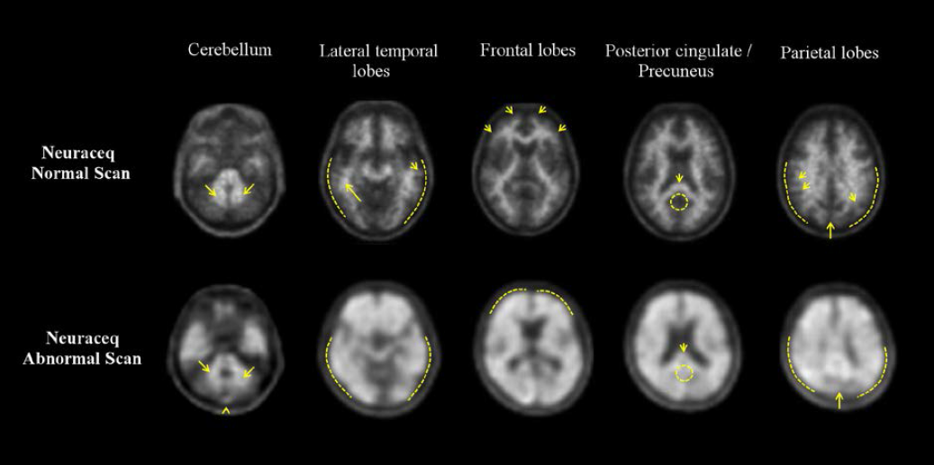

Florbetaben 顯像示意圖

商品名 Vizamyl Neuraceq

影像特性 偽彩色顯示、白質攝取較高 白質攝取較低、對比較明確

敏感性 / 特異性 約 81-93% / 44-92% 約 97.9% / 88.9%